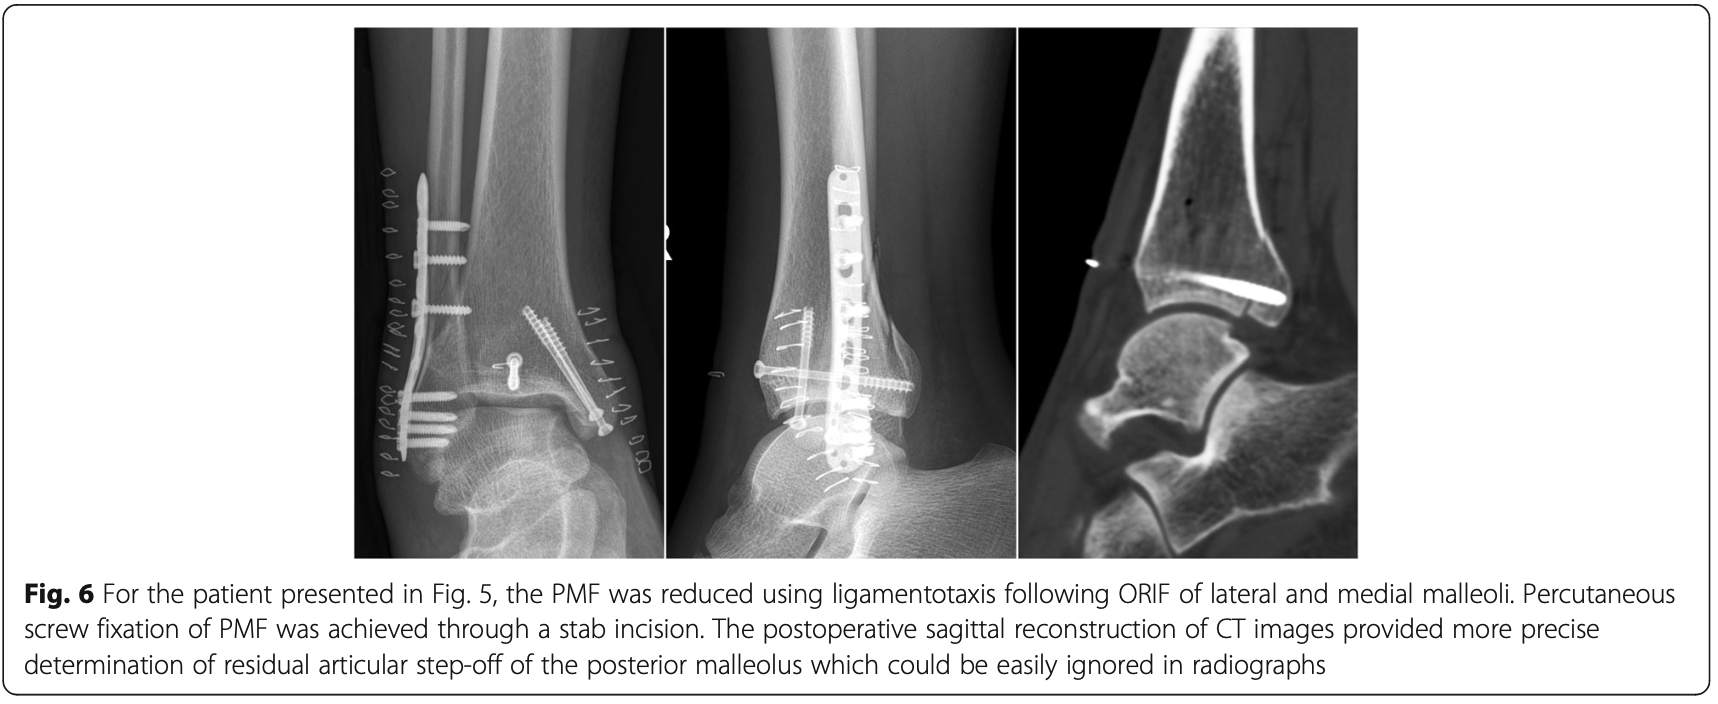

8時前に病棟に上がって, 昨日足関節三果骨折の手術が行われた中高年の患者さんの経過を夜勤の看護師さんから報告されました. 特に問題なく経過されていました.